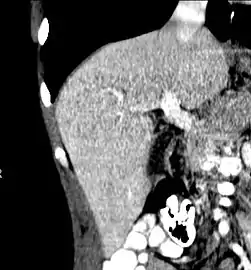

CT scan showing an adult liver in the axial plane

Organogenesis, the development of the organs, takes place from the third to the eighth week during embryogenesis. The origins of the liver lie in both the ventral portion of the foregut endoderm (endoderm being one of the three embryonic germ layers) and the constituents of the adjacent septum transversum mesenchyme. In the human embryo, the hepatic diverticulum is the tube of endoderm that extends out from the foregut into the surrounding mesenchyme. The mesenchyme of septum transversum induces this endoderm to proliferate, to branch, and to form the glandular epithelium of the liver. A portion of the hepatic diverticulum (that region closest to the digestive tube) continues to function as the drainage duct of the liver, and a branch from this duct produces the gallbladder.[35] Besides signals from the septum transversum mesenchyme, fibroblast growth factor from the developing heart also contributes to hepatic competence, along with retinoic acid emanating from the lateral plate mesoderm. The hepatic endodermal cells undergo a morphological transition from columnar to pseudostratified resulting in thickening into the early liver bud. Their expansion forms a population of the bipotential hepatoblasts.[36] Hepatic stellate cells are derived from mesenchyme.[37]